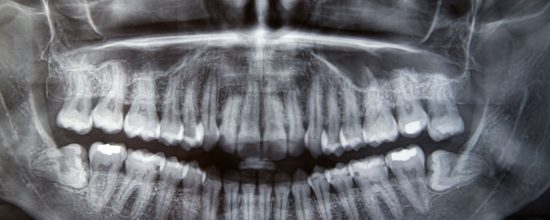

El hueso alveolar es como conocemos a la estructura ósea sobre la que se integran las raíces dentales. Junto con los tejidos gingivales mantienen a la pieza dental en su sitio y aseguran su estabilidad.

Sin embargo, son varios los motivos que pueden propiciar un desgaste en este hueso, que al principio es muy difícil de identificar pero que puede llegar a producir la pérdida de hasta un 60% de su altura y grosor en los 3 primeros años.

Ante la ausencia de una pieza dental, el hueso alveolar deja de recibir estímulos del masticado en la zona afectada. Esto provoca que comience esa reabsorción y comienza a producirse movilidad entre los dientes adyacentes. La solución ideal para esta situación pasa por un implante dental que vuelva a dar ese estímulo al hueso.

Enfermedad periodontal

Una periodontitis grave provoca que las bacterias formen sarro solidificado en capas bajo la encía. Este contacto bacteriano directamente con el hueso es el culpable de esa pérdida. Si se padece de enfermedad periodontal siempre debemos tener nuestra boca controlada por un periodoncista para evitar que la infección llegue a casos mayores como oeste.